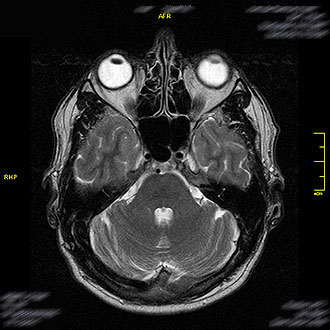

Die MRT Kopf ist eine der wichtigsten bildgebenden Untersuchungen in der modernen Radiologie. Im Kernspin Zentrum Köln wird die Magnetresonanztomographie (MRT) eingesetzt, um Gehirn, Nerven, Gefäße und Sinnesorgane hochauflösend und strahlungsfrei darzustellen. Sie ermöglicht eine sichere Diagnose bei Kopfschmerzen, Schwindel, Seh- oder Hörstörungen sowie neurologischen Erkrankungen.

Die MRT des Gehirns ist zentral für die neurologische Diagnostik. Im Kernspin Zentrum Köln wird sie zur Abklärung verschiedenster Beschwerden eingesetzt – von häufigen Kopfschmerzen und Migräne bis zu komplexen neurologischen Erkrankungen.

Die MRT ermöglicht es, selbst kleinste Veränderungen im Gehirn frühzeitig zu erkennen – ein entscheidender Vorteil für eine gezielte Therapie.